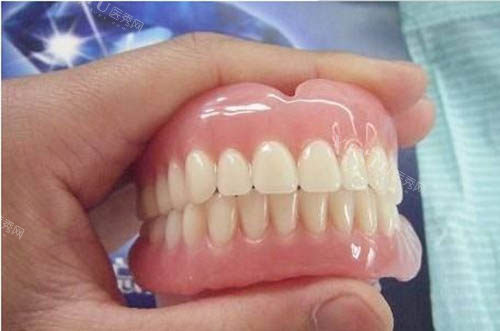

给老爷子看牙的是一位经验充足的医生,姓王。王医生特别有耐心,先是仔细地检查了老爷子口腔的情况,然后又问了问老爷子平时的身体状况和饮食习惯。接着,他跟我们详细地介绍了几种适合老爷子的假牙类型,什么活动假牙、固定假牙,每种假牙的优缺点、价格都讲得明明白白。

我们本来是倾向于活动假牙的,觉得方便清洁。但是王医生根据老爷子的口腔条件,建议我们选择固定假牙。他说老爷子的基牙条件还不错,固定假牙戴上之后更舒服,咀嚼功能也更好,虽然价格会高一些,但长远来看更合适。听了王医生的分析,我们觉得挺有道理,就决定听他的建议。

接下来就是制作假牙的过程了。医院的工作人员安排得很妥当,给老爷子取了牙模,还让我们留下联系方式,说做好了会头一时间通知我们。大概过了一周左右,我们就接到了医院的电话。再次来到医院,王医生亲自给老爷子安装假牙。安装的过程中,他不断地询问老爷子的感受,调整假牙的位置,确保老爷子戴着舒服。

安装好之后,老爷子试着咬了咬东西,脸上立马露出了笑容,说感觉好多了,吃东西也不费劲了。我看着老爷子开心的样子,心里也踏实了。而且,医院还跟我们说了一些假牙的保养方法,让我们有什么问题随时联系他们。